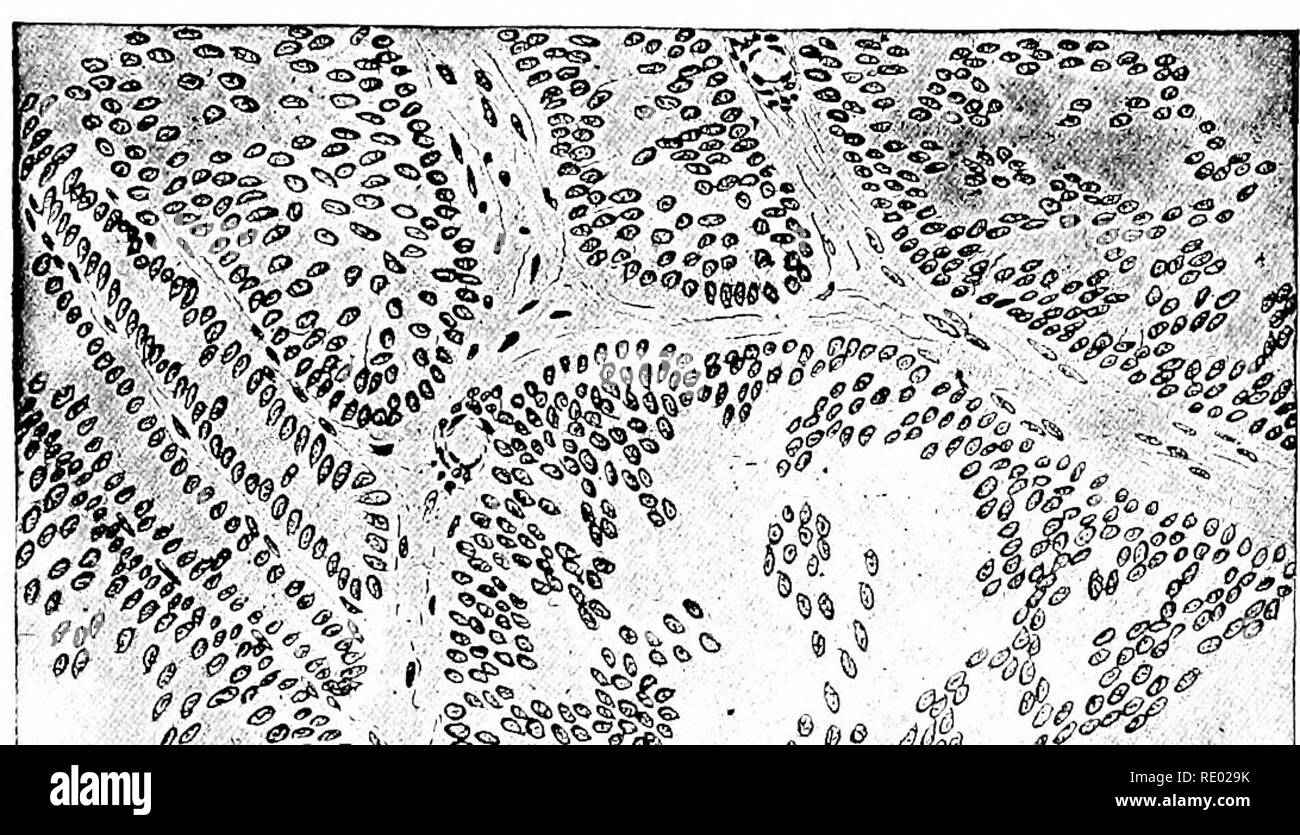

Mesothelium Tissue - Diverse Properties Of The Mesothelial Cells In Health And Disease / Binucleation, multinucleation, mitosis, prominent nucleolus can be seen in benign proliferations.. The pleura is the part of the mesothelium surrounding the lungs. The mesothelium is composed of an extensive monolayer of specialized cells (mesothelial cells) that line the body's serous cavities and internal organs. Here you can create your own quiz and questions like this consists of mesothelium and connective tissue. 2 words related to mesothelium: Epithelium (/ ˌ ɛ p ɪ ˈ θ iː l i ə m /) is one of the four basic types of animal tissue, along with connective tissue, muscle tissue and nervous tissue.it is a thin, continuous, protective layer of cells.epithelial tissues line the outer surfaces of organs and blood vessels throughout the body, as well as the inner surfaces of cavities in many internal organs.

Binucleation, multinucleation, mitosis, prominent nucleolus can be seen in benign proliferations. However, fat is the most common tissue invaded by these cells. 12 cells is unusual in simple hyperplasia. B heatmap of differentially expressed genes in the two comparisons crocidolite vs. The following tables show the different kinds of tumors each of the following tissue types are vulnerable to: Uterus, human, early proliferative, h&e digitalscope this is section of the uterus just after completion of menstruation and the beginning of the proliferative phase in which the uterine mucosa and glands regenerate. The mesothelium is composed of an extensive monolayer of specialized cells (mesothelial cells) that line the body's serous cavities and internal organs. mesothelium is composed of specialized mesothelial cells, which are found as a monolayer of squamous epithelial cells lining the basement membrane and supported by dense irregular connective tissue. Another portion of the mesothelium wraps around the heart; It has high capacity of regeneration ranging from few days to even. While some have suggested that white adipose tissue (wat) adipocyte progenitors are The lining of the tissue is developed by the mesothelial cells. This portion of the protective tissue is called the peritoneum, or peritoneal mesothelium.

mesothelium is composed of specialized mesothelial cells, which are found as a monolayer of squamous epithelial cells lining the basement membrane and supported by dense irregular connective tissue.

Each lung projects into an internal body cavity, the pleural cavity, and is covered by a serous membrane (serosa), called visceral pleura. The following tables show the different kinds of tumors each of the following tissue types are vulnerable to: The mesothelium is a membrane that forms the lining of several body cavities: These questions will build your knowledge and your own create quiz will build yours and others people knowledge. The mesothelium is a membrane that forms the lining of several body cavities: These two layers of tissue comprise the pleura, or pleural mesothelium. Mesothelial tissue also surrounds the male internal reproductive organs and covers the internal reproductive organs of women. Binucleation, multinucleation, mitosis, prominent nucleolus can be seen in benign proliferations. This tissue is known as the pericardium. The main risk factor for pleural mesothelioma is exposure to asbestos, which for most people occurred at work. Pleura is composed of a simple squamous epithelium (mesothelium) overlying a layer of connective tissue that contains blood vessels and elastic fibers. Another portion of the mesothelium wraps around the heart; The mechanical testing of the mesothelium tissue is difficult, as it is a single layer of flattened cells, 2.5 to 3 μm in thickness, which is difficult to remove intactly from the bottom layer of the fibrous connective tissue.